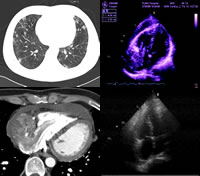

2.超聲都卜勒血流計檢查和阻抗容積描記術前者根據超音波遇到運動目標(靜脈血流中的血球)而反射時發生頻率變化且與運動速度成比例的特性;後者根據正常狀態下,肢體血容量隨呼吸時靜脈壓力的改變而變化的特性;用電阻抗技術查知這些微小的容量變化引起的電壓變化在主要血管阻塞時,肢體容積不隨呼吸而變化,因而沒有電壓變化這兩種方法簡便,無創傷,可以反映靜脈的機能狀態但準確性較差尚不能檢查出小血栓和閉塞的靜脈以及側支循環豐富部位的血栓。

3.紅外線顯像(thermography)是深靜脈血栓形成的無創傷檢查法,該法輔以容積描記與靜脈造影相比可以發現深靜脈血栓形成達95%紅外線顯像與靜脈造影的符合率達85%

4.靜脈造影經足背皮靜脈或於跟骨髂腔內入造影劑然後對下肢攝片該法能檢出約90%的小腿靜脈血栓能確定血栓的部位和範圍動態靜脈造影可以推測靜脈瓣功能。